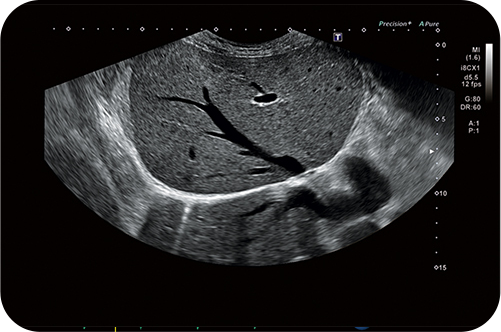

Технически совершенная система УЗИ #1

✅ Архитектура визуализации Crystal Architecture™✅ Быстрый рендеринг: в три раза больше память графического процессора

✅ Высококачественные изображения: в 11(!) раз большая вычислительная мощность

✅ Высокая частота кадров: в 10 раз увеличенная скорость передачи данных

✅ Детальное выражение динамики кровотока с CrystalLive™